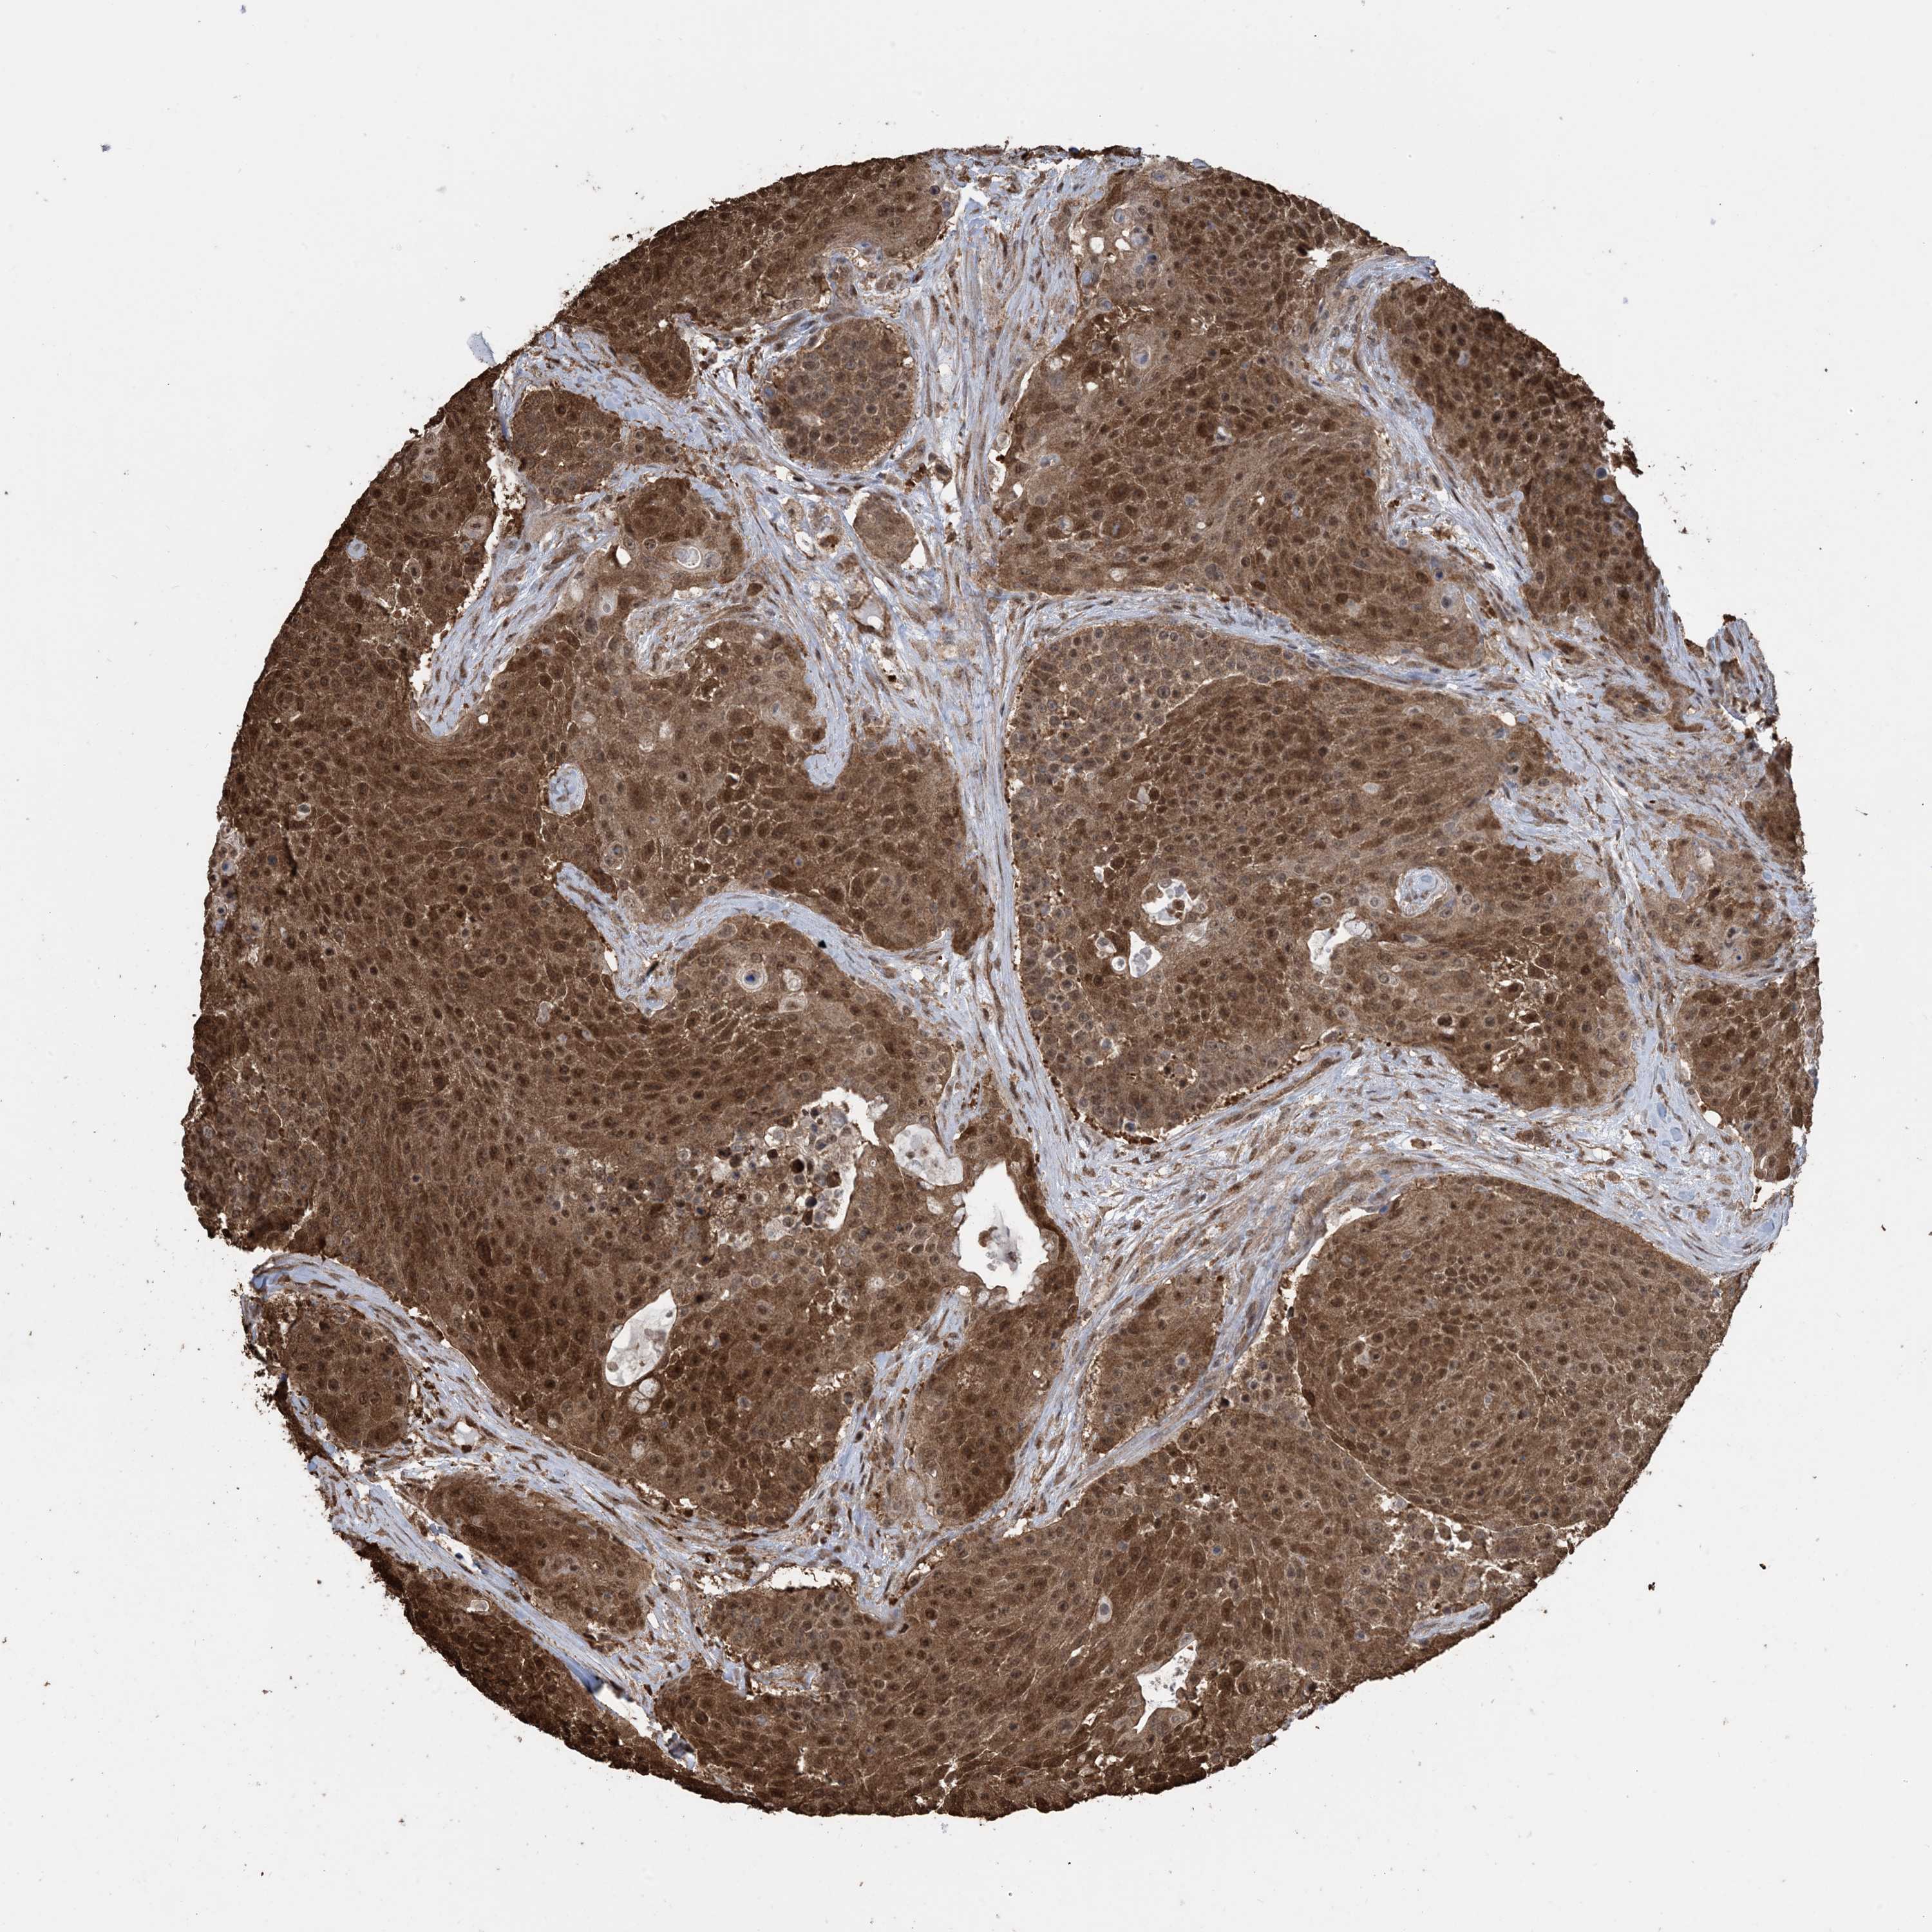

UROTHELIAL CANCER - Protein expressioni

A mouse-over function shows sample information and annotation data. Click on an image to view it in a full screen mode. Samples can be filtered based on level of antibody staining by selecting one or several of the following categories: high, medium, low and not detected. The assay and annotation is described here.

Note that samples used for immunohistochemistry by the Human Protein Atlas do not correspond to samples in the TCGA dataset.

Antibody stainingi

Antibody staining in the annotated cell types in the current human tissue is reported as not detected, low, medium, or high, based on conventional immunohistochemistry profiling in selected tissues. This score is based on the combination of the staining intensity and fraction of stained cells.

Each image is clickable and will lead to virtual microscopy that enables deeper exploration of all samples and also displays staining intensity scores, fraction scores and subcellular localization as well as patient and tissue information for each sample.

Antibody HPA052504

Antibody CAB017451

Antibody CAB032815

Staining

High

Medium

Low

Not detected

Intensity

Strong

Moderate

Weak

Negative

Quantity

>75%

75%-25%

<25%

None

Location

Nuclear

Cytoplasmic/membranous

Cytoplasmic/membranous,nuclear

Urothelial carcinoma, High grade

Urothelial carcinoma, NOS

Urothelial carcinoma, Low grade